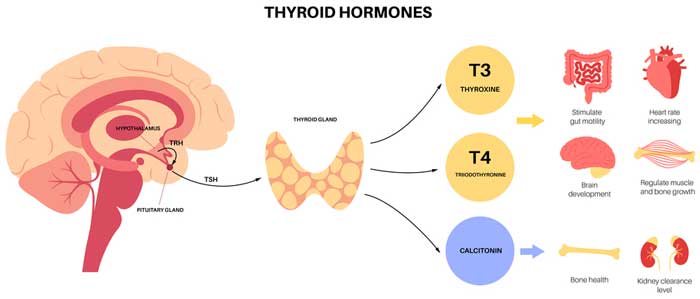

Let’s start with the basics: your thyroid plays a significant role in keeping your body running smoothly. When it’s underactive, as in hypothyroidism, medications like levothyroxine provide a much-needed boost of thyroid hormones.

Before diving into strategies, it’s important to understand how hypothyroidism and its treatment can affect your bones. The connection lies in your thyroid hormone levels. When these levels are too high—a condition called subclinical hyperthyroidism—it can accelerate the breakdown of bone tissue. This is why your medication dosage needs to be carefully balanced. Too much thyroid hormone can strain your bones, while too little can leave you feeling fatigued, sluggish, and unwell.